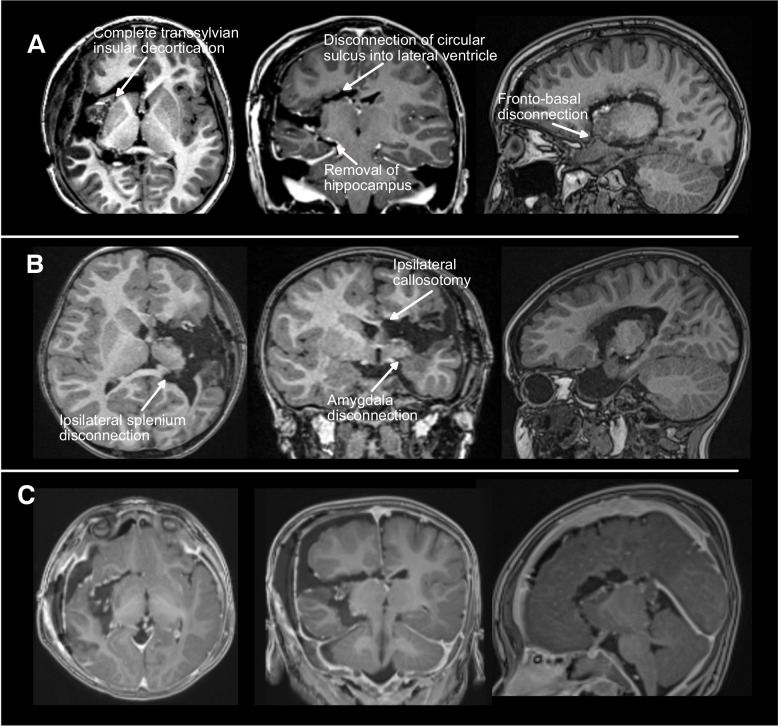

Purpose: Hemispherotomy is an effective treatment for well-selected patients with drug-resistant hemispheric epilepsy. Successful hemispherotomy leading to seizure cessation has been associated with improved neurodevelopmental outcomes and reduced healthcare utilization. This study reports seizure outcomes and complications in a large, consecutive, single-surgeon series of pediatric hemispherotomy cases using a surgical approach with modifications to previously-reported techniques.

Methods: All patients undergoing transsylvian peri-insular hemispherotomy for drug-resistant hemispheric epilepsy between May 2017 and April 2021 by a single surgeon were prospectively enrolled in an epilepsy surgery registry. With retrospective review of medical records, data were collected on baseline characteristics (demographics, epilepsy history, anti-seizure medications, neurodevelopmental status, EEG features, and imaging characteristics), operative complications, hospital course, and seizure outcomes (Engel scale at 12- and 24-month follow-up).

Results: All 32 consecutive patients (aged 15 months-19 years) were seizure-free (Engel Class 1) 12 and 24 months after hemispherotomy. At 12 months, 31 patients (97%) had Engel Class 1A outcomes, and 1 patient (3%) had an Engel Class 1D outcome. These results were maintained through 24-month follow-up. Among 31 patients taking anti-seizure medications before surgery, 22 (71%) were weaned off all agents by 24 months. One patient (3%) developed post-operative hydrocephalus requiring ventriculoperitoneal shunt placement.

Conclusion: In an etiologically heterogeneous cohort of patients undergoing hemispherotomy for drug-resistant epilepsy, a modified transsylvian peri-insular technique led to high rates of sustained seizure freedom with minimal complications.